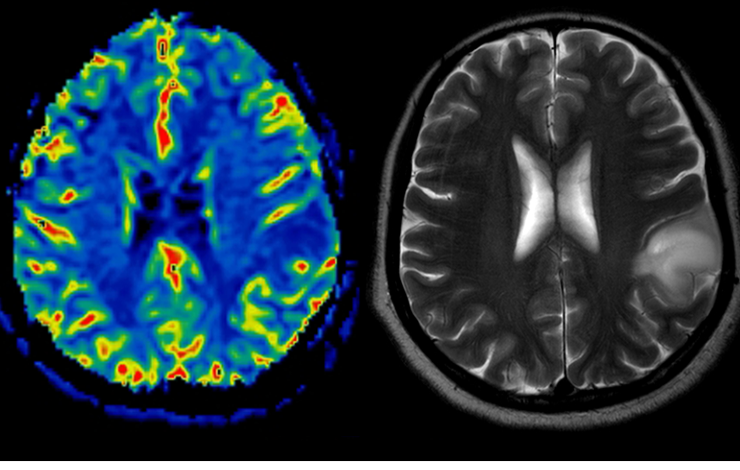

​​Des chercheurs du CEA-Joliot ont développé en collaboration avec l'université et l'hôpital de Tours une méthode de détection de tumeurs cérébrales qui repose sur l'analyse des vibrations naturelles produites dans le corps. Appelée élastographie passive par résonance magnétique, la méthode est inspirée des outils d'analyse des sismologues et offre l'avantage de ne pas nécessiter l'utilisation d'une source de vibrations externes au corps. Elle a déjà prouvé son efficacité en essai clinique.​​​

L'élastographie passive par résonance magnétique (pMRE) est une méthode d'imagerie médicale qui permet d'évaluer l'élasticité (également appelée dureté) des tissus biologiques et organes. Cette méthode permet entre autres de détecter des tumeurs qui ont une dureté différente des tissus sains. Inspirée de notions de tomographie par corrélation de bruit utilisées en sismologie (technique d'imagerie qui permet de reconstituer le volume d'un objet à partir de la mesure des ondes à sa surface), elle consiste à analyser les vibrations naturelles du corps, comme celles induites par les battements du cœur ou la respiration. L'approche développée en collaboration avec le LabTau (Inserm, Université Lyon 1) permet alors d'estimer la dureté via le bruit généré par ces vibrations sur l'image IRM acquise..

Dans leur étude, les chercheurs de BioMaps et de NeuroSpin (CEA-Joliot) en collaboration avec l'hôpital de Tours et iBraiN (université de Tours) ont conçu et développé une séquence innovante de pMRE, dans le cadre d'un essai clinique mené chez 18 patients porteurs de différents types de tumeurs cérébrales (12 porteurs de tumeurs malignes et 6 de tumeurs bénignes).

Ils ont comparé les résultats pMRE aux paramètres mesurés par une élastographie par ultrasons  réalisée en échographie pendant la résection chirurgicale de la tumeur et ont constaté que les valeurs de longueur d'onde des tumeurs obtenues par pMRE étaient significativement corrélées à celles obtenues par l'élastographie ultrasonore. De manière tout à fait intéressante, la pMRE a permis, via la mesure de la longueur d'onde, de distinguer les tumeurs malignes des tumeurs bénignes.